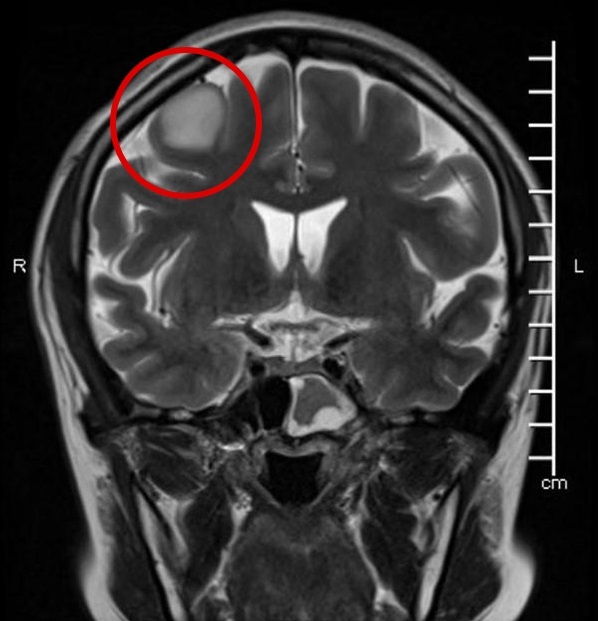

Hình chụp MRI ở 2 mặt cắt hộp sọ. |

Qua thăm khám và chỉ định chụp MRI, bác sĩ nhận thấy khối choán chỗ trong trục vùng trán phải, kích thước khoảng 2,5 cm. Tiên lượng đây là khối u sao bào độ ác tính thấp, bác sĩ Chu Tấn Sĩ tư vấn bệnh nhân nhập viện để phẫu thuật.